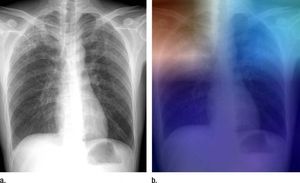

Röntgen (links) und Analyse über Künstliche Intelligenz (Foto: rsna.org) |

Philadelphia (pte001/26.04.2017/06:00) Forscher des Thomas Jefferson University Hospital (TJUH) http://hospitals.jefferson.edu trainieren Künstliche Intelligenz (KI) dahin, Tuberkulose (TBC) auf Röntgenaufnahmen des Brustkorbs zu erkennen. Damit ließen sich Screenings und Evaluierungsbemühungen in Regionen mit eingeschränktem Zugang zu Radiologen verbessern. Die Ergebnisse wurden im Fachmagazin "Radiology" publiziert.

Bei Deep Learning handelt es sich um eine KI-Art, die es Computern ermöglicht, Aufgaben basierend auf den bestehenden Beziehungen von Daten zu lösen. Ein Deep Convolutional Neural Network (DCNN) nutzt mehrfache verborgene Schichten und Muster, um Abbildungen zu klassifizieren. Lakhani und Mitautor Baskaran Sundaram haben 1.007 Röntgenbilder von Patienten mit und ohne aktiver TBC genutzt. Die Daten stammen von Untersuchungen der National Institutes of Health, des Belarus Tuberculosis Portal und des TJUH.

Die Datensätze wurden in drei Bereiche aufgeteilt: Training (68 Prozent), Überprüfung (17,1 Prozent) und Test (14,9 Prozent). Die Fälle wurden eingesetzt, um mit AlexNet und GoogLeNet zwei verschiedene DCNN-Systeme zu trainieren, die von negativen und positiven Röntgenbildern lernten. Die Genauigkeit der Modelle wurde an 150 Fällen getestet, die aus den anderen Datensätzen ausgeschlossen wurden.

Am besten schnitt eine KI-Form mit einer Genauigkeit von 96 Prozent ab, die aus einer Kombination von AlexNet and GoogLeNet bestand. "Die Anwendbarkeit für TBC ist wichtig, da es sich um eine Krankheit handelt, die behandelt werden kann. Das ist ein Problem, das sich lösen lässt", so Lakhani. Die beiden DCNN-Modelle waren sich bei 13 der 150 Testfälle nicht einig. Für diese Fälle evaluierten die Forscher einen Workflow, bei dem ein Experte die Bilder zu 100 Prozent korrekt diagnostizieren konnte. Dieser Workflow, bei dem ein menschlicher Experte hinzugezogen wird, konnte eine Genauigkeit von fast 99 Prozent erreichen.